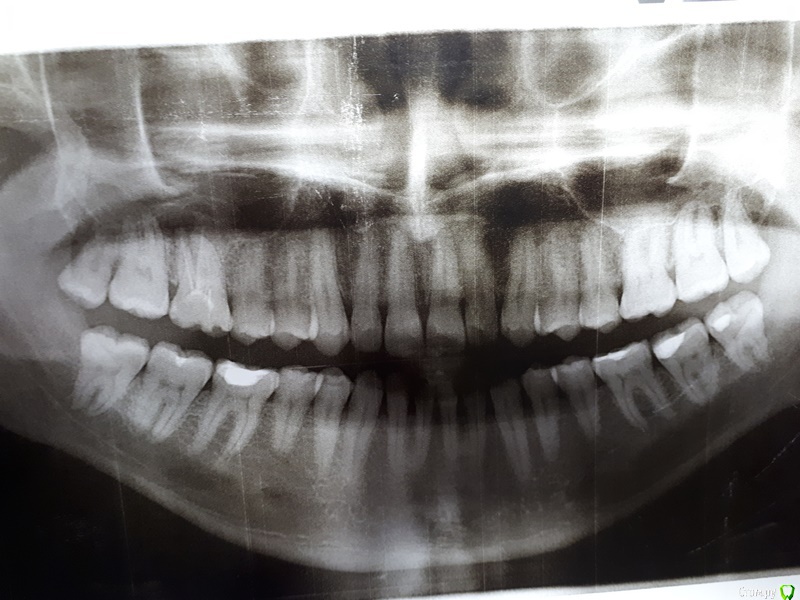

vchistyakov Опубликовано 13 декабря, 2017 Поделиться Опубликовано 13 декабря, 2017 Уважаемые специалисты! Спешу к вам за профессиональным мнением и советом. Хроника вопроса выглядит следующим образом: 1) Имеем зуб, шестёрка верхняя справа. Иногда тянущее ощущение почти у основания десны (обычно утром пока не поднялся). При нажатии на эту область двумя пальцами ощущения лёгкое болевое ощущение. В основании десны (где начинается верхняя губа) языком прощупывается комочкообразное уплотнение. 2) Ортопантомограмма сделана. В местах где делал, сказали, что есть подозрения на кисту. Фото в прикреплении. 3) Стоматолог-терапевт отправил на рентген отдельного зуба. Делали два раза, ничего не увидел. Посоветовал сделать КТ. 4) КТ сделано, стоматолог-терапевт снова в нём кисту не видит. Говорит, что корни влезли в пазуху и лучше зуб не трогать вообще, а кисты нет. Архив сейчас можно скачать по ссылке (https://drive.google.com/drive/folders/1P3iMeAWCg0PXtU2NDpLzwrDNNR52io5_?usp=sharing). Скриншот с КТ в трёх плоскостях прикрепляю вместе с сообщением. Своему стамотологу-терапевту доверяю как специалисту, т.к. хороший профессионал. В этом вопросе хочу узнать мнение как можно большего количества специалистов. Спасибо большое заранее. Ссылка на комментарий

АнтонТЛТ Опубликовано 13 декабря, 2017 Поделиться Опубликовано 13 декабря, 2017 Как кисту такого размера можно не увидеть... 2 Ссылка на комментарий

vchistyakov Опубликовано 13 декабря, 2017 Автор Поделиться Опубликовано 13 декабря, 2017 Как кисту такого размера можно не увидеть... :-( не знаю. То, что я сам увидел, меня очень расстроило. Но врач сказал, что самостоятельно результаты КТ смотреть не стоит. Значит киста очевидная? Какие дальнейшие шаги? Ссылка на комментарий